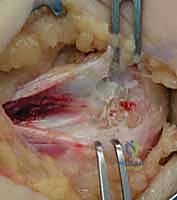

Ulnar Nerve Management

The most critical step prior to fracture manipulation is the identification and protection of the ulnar nerve. The nerve is located posterior to the medial epicondyle within the cubital tunnel. The fascia over the nerve is carefully incised.

* In Situ Decompression vs. Transposition: If the nerve is structurally intact, uninjured, and not under tension upon reduction of the fracture, an in situ decompression is generally sufficient. However, if the nerve is severely contused, incarcerated within the joint, or if the hardware placement threatens to impinge upon the cubital tunnel, a formal anterior subcutaneous or submuscular transposition should be performed. If transposed, the medial intermuscular septum must be excised to prevent kinking of the nerve.

Fragment Retrieval and Joint Debridement

If the fragment is incarcerated within the joint, blind levering must be strictly avoided to prevent iatrogenic chondral damage. A gentle valgus stress is applied to the elbow while supinating the forearm; a dental pick or fine nerve hook can then be used to carefully tease the fragment out of the joint space. Once the fragment is mobilized, the fracture bed on the distal humerus is thoroughly debrided of hematoma, interposed periosteum, and fibrous debris using a curette to expose bleeding cancellous bone, optimizing the biological environment for union.

Reduction and Provisional Fixation